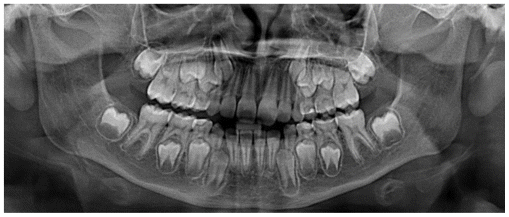

Case 3

The patient was a 6-year-old female presenting with a Class III dento-skeletal malocclusion associated with anterior crossbite in the early mixed dentition (Figures 20–26). Baseline diagnostic records included orthopantomography, latero-lateral cephalometric radiography with cephalometric analysis, and extraoral and intraoral photographs. Clinical examination revealed a flat-to-slightly convex facial profile with sagittal skeletal discrepancy and negative overjet (Tables 5, 6). The treatment consisted exclusively of functional orthopedic therapy using the AMCOP® TC appliance, worn throughout the night and for one additional hour during the day, for a total duration of 24 months. At the end of active treatment, complete correction of the anterior crossbite was achieved, with normalization of overjet and overbite and establishment of a Class I dental relationship. A long-term follow-up evaluation performed at the age of 12 years, in complete permanent dentition, confirmed the stability of the results, showing a well-maintained anterior dental seal and a stable Class I occlusion. The AMCOP® TC appliance was continued as nighttime retention only, supporting neuromuscular balance and occlusal stability throughout growth.